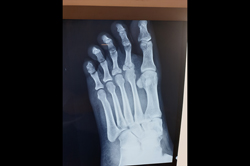

Metarsals with dislocations Lisfranc